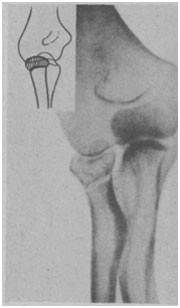

Все переломы головки и шейки можно разделить на три группы: переломы головки (рис. 32), переломы шейки (рис. 33) и переломы головки и шейки. При переломах головки различают переломы со смещением и без смещения, краевые переломы, оскольчатые переломы. Переломы шейки бывают со смещением головки и вколоченные. У детей и подростков наблюдаются эпифизеолизы.

Рис. 33. Перелом шейки лучевой кости.